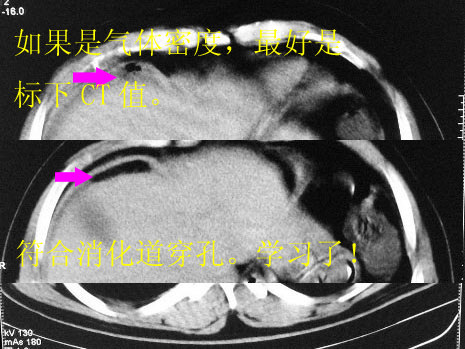

腹痛5小时,来院就诊,腹部平片提示肠管积气,肠管扩张,建议ct检查.

消化道穿孔

考虑1、消化道穿孔;2、不除外间位结肠?

结肠脾区肠壁水肿,周围低密度包绕,此处穿孔可能.

穿孔!有ct值或换个体位更能说明问题